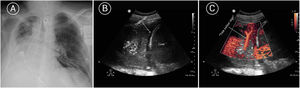

On day 22 of admission, he experienced sudden respiratory and hemodynamic worsening, with a need for vasoactive drugs and increased FiO2 demands. There was no fever or elevation of infection markers. Echocardiography discarded indirect signs of pulmonary thromboembolism. The chest radiography (Fig. 1 Image A) evidenced a clear worsening of the right hemithorax. Pulmonary ultrasound in turn revealed a pattern C (Fig. 1 Image B) in the right lung base that could correspond to atelectasis or pneumonia. Color Doppler (Appendix A image C and enclosed video) revealed a tree-like color sign, corresponding to blood hyper-flow. This finding, together with the dynamic pattern C (fluctuating with inspiration) was consistent with pneumonic condensation.